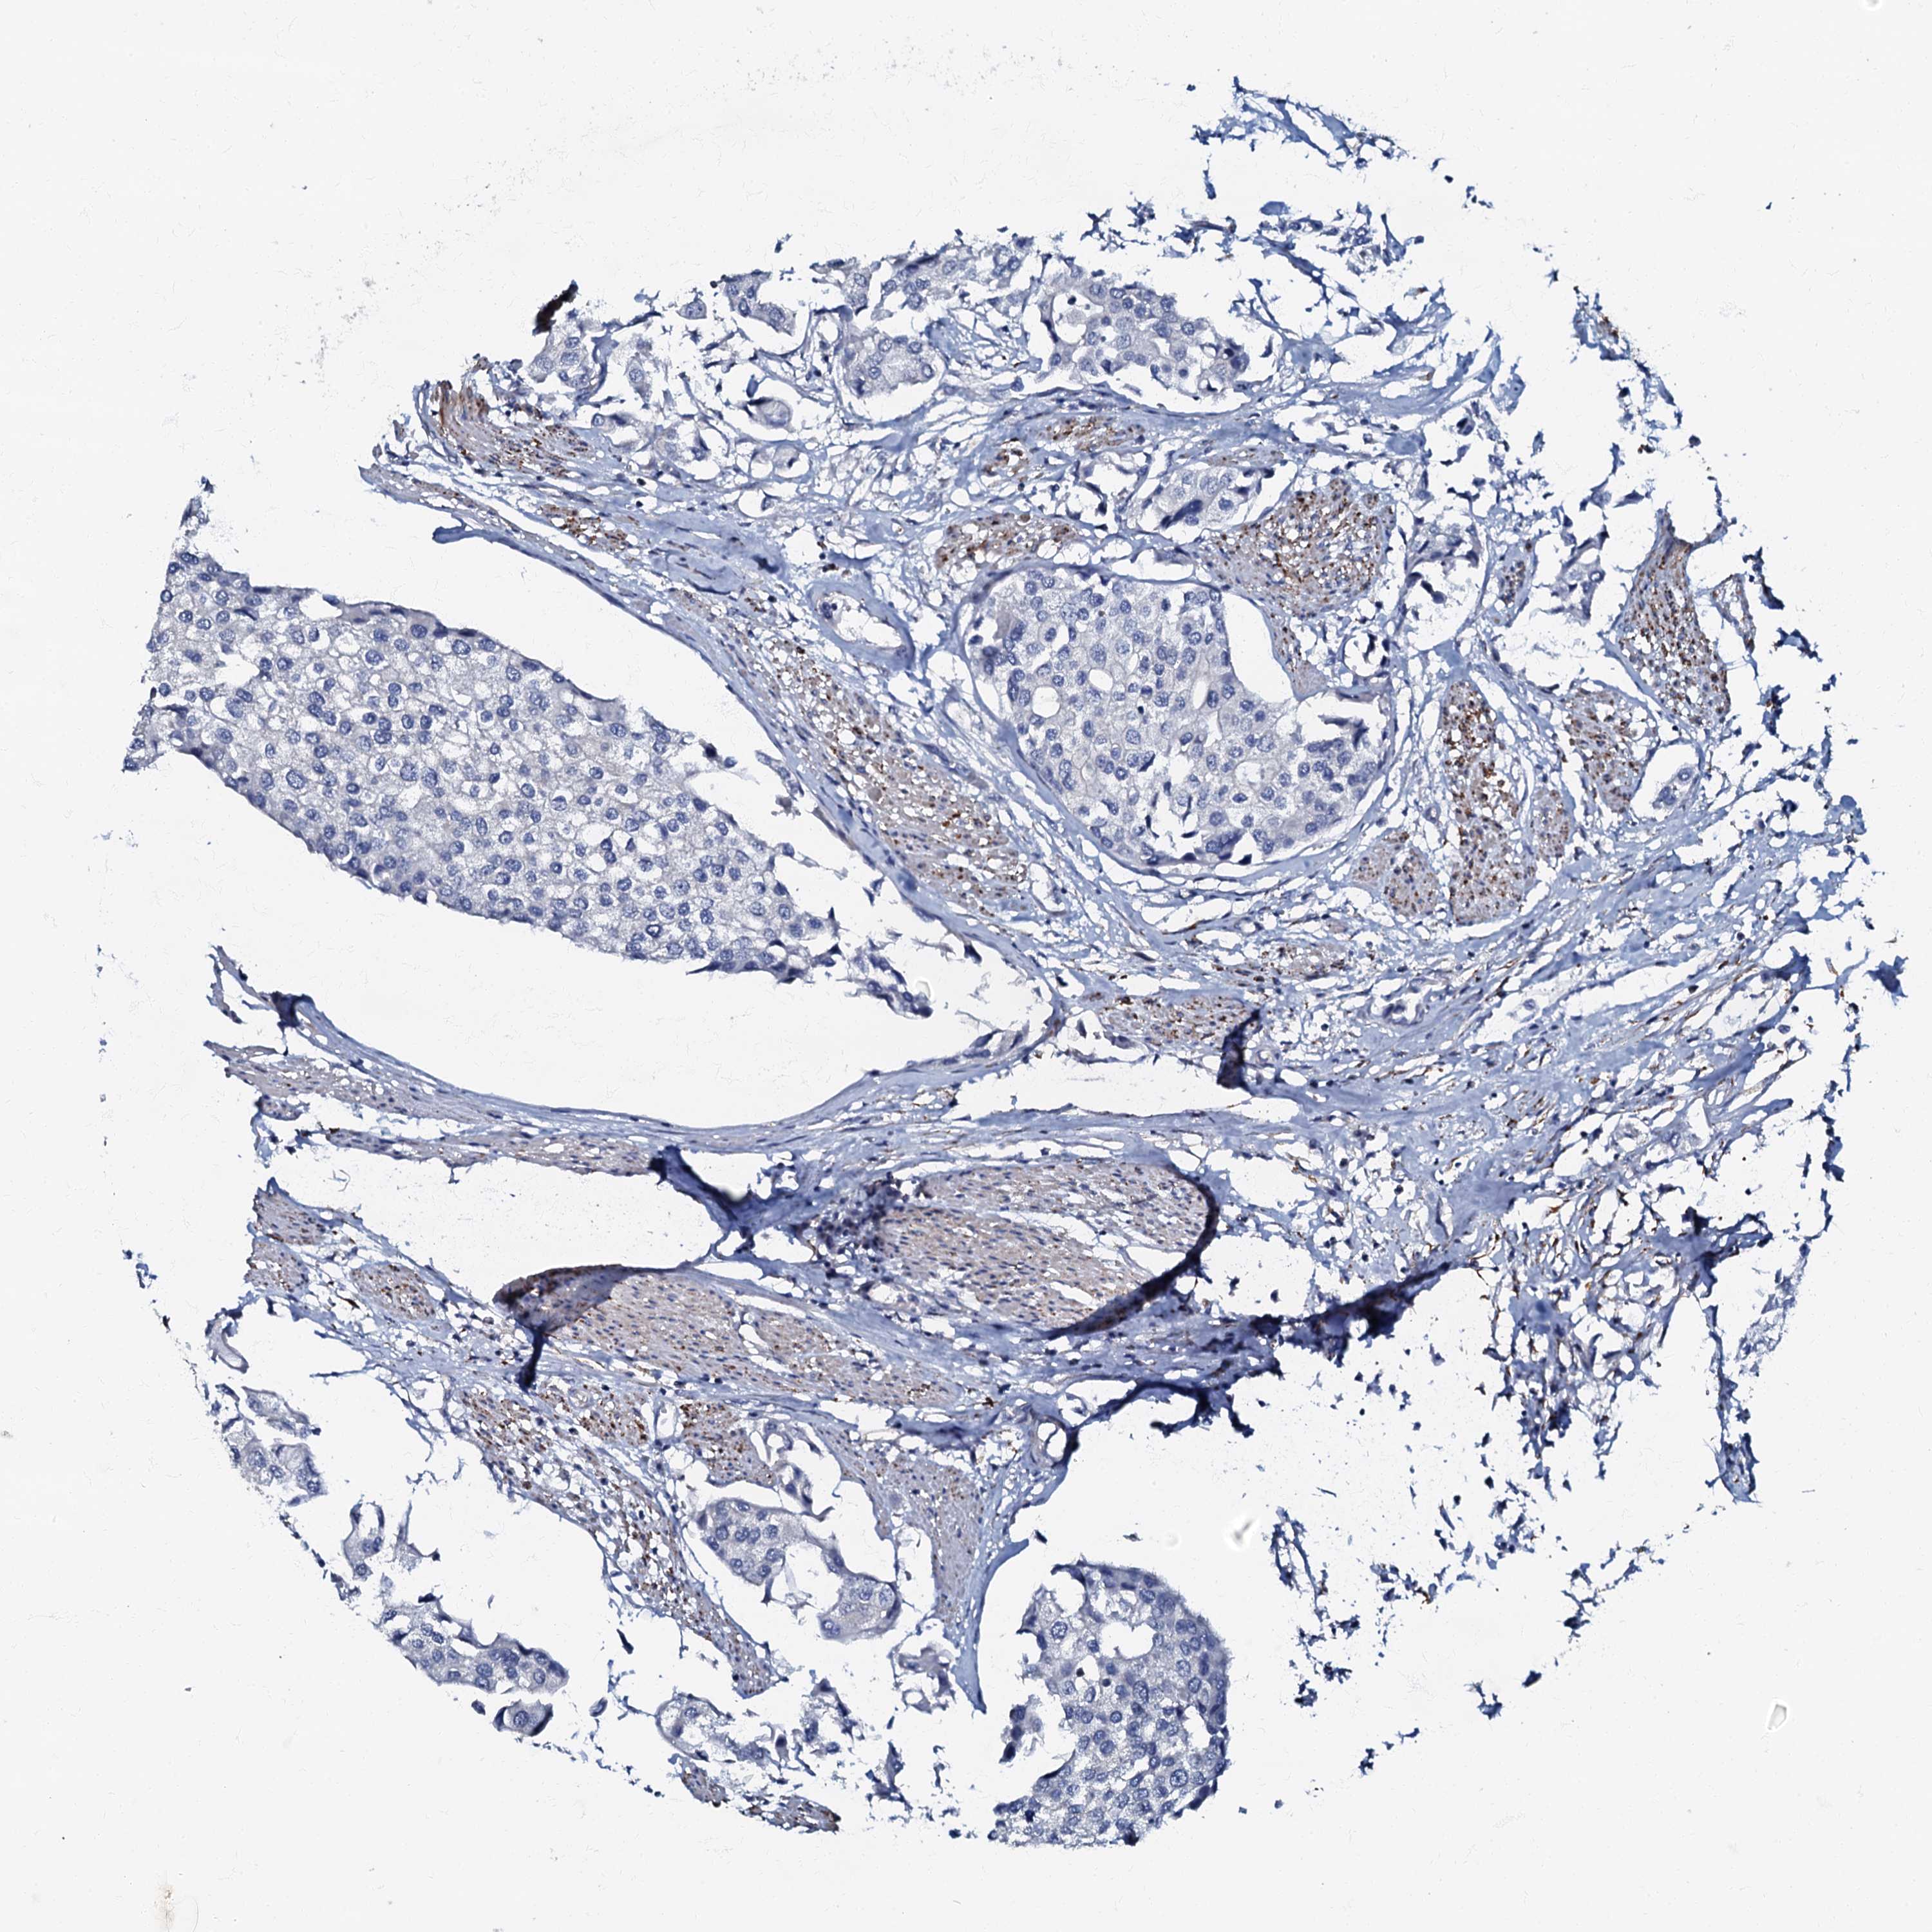

UROTHELIAL CANCER - Protein expressioni

A mouse-over function shows sample information and annotation data. Click on an image to view it in a full screen mode. Samples can be filtered based on level of antibody staining by selecting one or several of the following categories: high, medium, low and not detected. The assay and annotation is described here.

Note that samples used for immunohistochemistry by the Human Protein Atlas do not correspond to samples in the TCGA dataset.

Antibody stainingi

Antibody staining in the annotated cell types in the current human tissue is reported as not detected, low, medium, or high, based on conventional immunohistochemistry profiling in selected tissues. This score is based on the combination of the staining intensity and fraction of stained cells.

Each image is clickable and will lead to virtual microscopy that enables deeper exploration of all samples and also displays staining intensity scores, fraction scores and subcellular localization as well as patient and tissue information for each sample.

Antibody HPA037947

Antibody HPA037948

Staining

High

Medium

Low

Not detected

Intensity

Strong

Moderate

Weak

Negative

Quantity

>75%

75%-25%

<25%

None

Location

Nuclear

Cytoplasmic/membranous

Cytoplasmic/membranous,nuclear

Urothelial carcinoma, High grade

Urothelial carcinoma, Low grade

Urothelial carcinoma, NOS